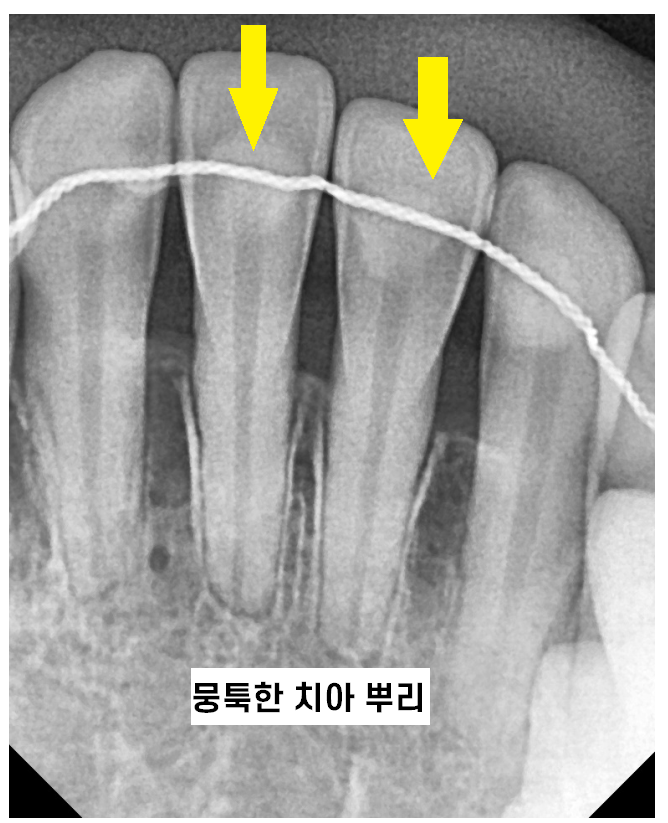

250103 x-ray를 보고 확인하죠~

때로는 3)선천적으로 치아 뿌리가 짧은 환자분들도 있어요!

241022 겉으로는 전혀 치근흡수가 일어났는지 알 수 없어요

치아 뿌리 짧아짐은 대부분 1-2mm 정도의 미세한 변화이고

오실때마다 x ray 검사를 합니다.

과교정이 되고 있거나

치아 뿌리가 짧아지는듯 하면 교정력을 조정하면서

치아 뿌리를 최대한 보존하는데요.